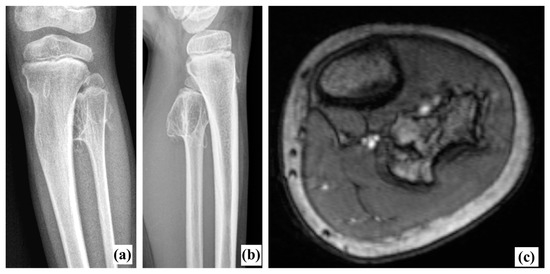

Radiography (Figure 1a,b) revealed a voluminous inter-tibio-fibular osteochondroma developed from fibular proximal metaphysis. The approximate dimensions of the bone tumor were about 4/3/2 cm (cranio-caudal/antero-posterior/latero-lateral). The lesion had all the characteristics of an exostosis [3]: benign-appearing bone lesion, bony excrescence with well-defined margins, thin outer cortex which flares from the host bone cortex and internal lesion in cancellous bone which blends with the cancellous bone of the metaphysis [3]. There was no sign of adjacent bone scalloping, but bowing of the tibia was present. We also performed an MRI exam which confirmed the lesion and showed close relation to the tibiofibular trunk and the anterior tibial artery, but without any sign of compression (Figure 1c). Long-leg radiographs showed valgus deformity of the tibia (HKA angle: 166°, MAD: 29 mm) (Figure 2).

As for follow-up, the patient was evaluated every six weeks during the first three months and every six months until the first two years after surgery. The patient presented a gradual improvement of the valgus deformity. At 27 months postoperative, he was asymptomatic with a full range of motion of the knee, no clinical deformity and no knee frontal laxity. Long-leg radiographs showed the complete correction of the tibia valga (HKA: 178° AND MAD < 5 mm) (Figure 2, Table 1). Notably, due to extraperiosteal resection, there was no sign of bone union at the proximal fibula. Tibial bowing improved as well (Figure 4). Lateral release of the fibula led to an increase in the fibula/tibia index (from 93% preop to 96% at follow-up), resulting in valgus deformity improvement (Figure 5, Table 1). Using a Pearson correlation test, we found that HKA and fibula/tibia index were strongly correlated (R = 0.9390, p < 0.001).

Figure 2. Long-leg X-rays showing gradual improvement of valgus deformity throughout follow-up.